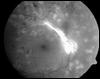

Dank der Möglichkeiten der Lasertherapie kann bei rechtzeitigem Beginn das Schicksal, durch diabetische Retinopathie zu erblinden, vermieden werden. Wenn eine Laserbehandlung erforderlich ist, kann diese nach Fluoreszenzangiographie gezielt eingesetzt werden. Die Behandlung ist gut verträglich und nicht schmerzhaft.

Folgen eines zu späten Behandlungsbeginns dieser Erkrankung können zu Sehschärfenverlust bis zur Erblindung, Katarakt (grauer Star) und Glaukom (grüner Star) sowie Glaskörpereinblutung und Netzhautablösung führen. Einblutungen des Glaskörpers durch defekte Gefäße können Vitrektomien (Glaskörperentfernungen) und Silikonölfüllungen des Auges erfordern. Rechtzeitige Vorsorge und Behandlung helfen diese Operationen vermeiden.